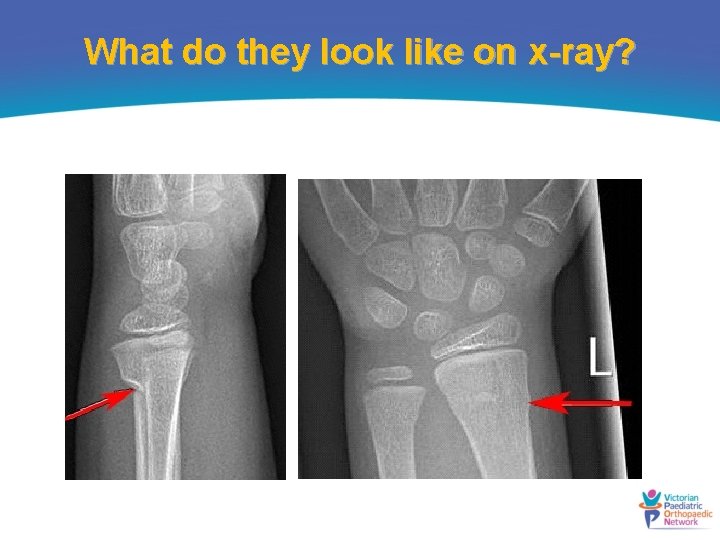

What do they look like on x-ray?

How are they classified? • Occur in the metaphyseal region of the distal radius • Compression injury and stable • Need to be distinguished from complete fractures, greenstick fractures and growth plate fractures